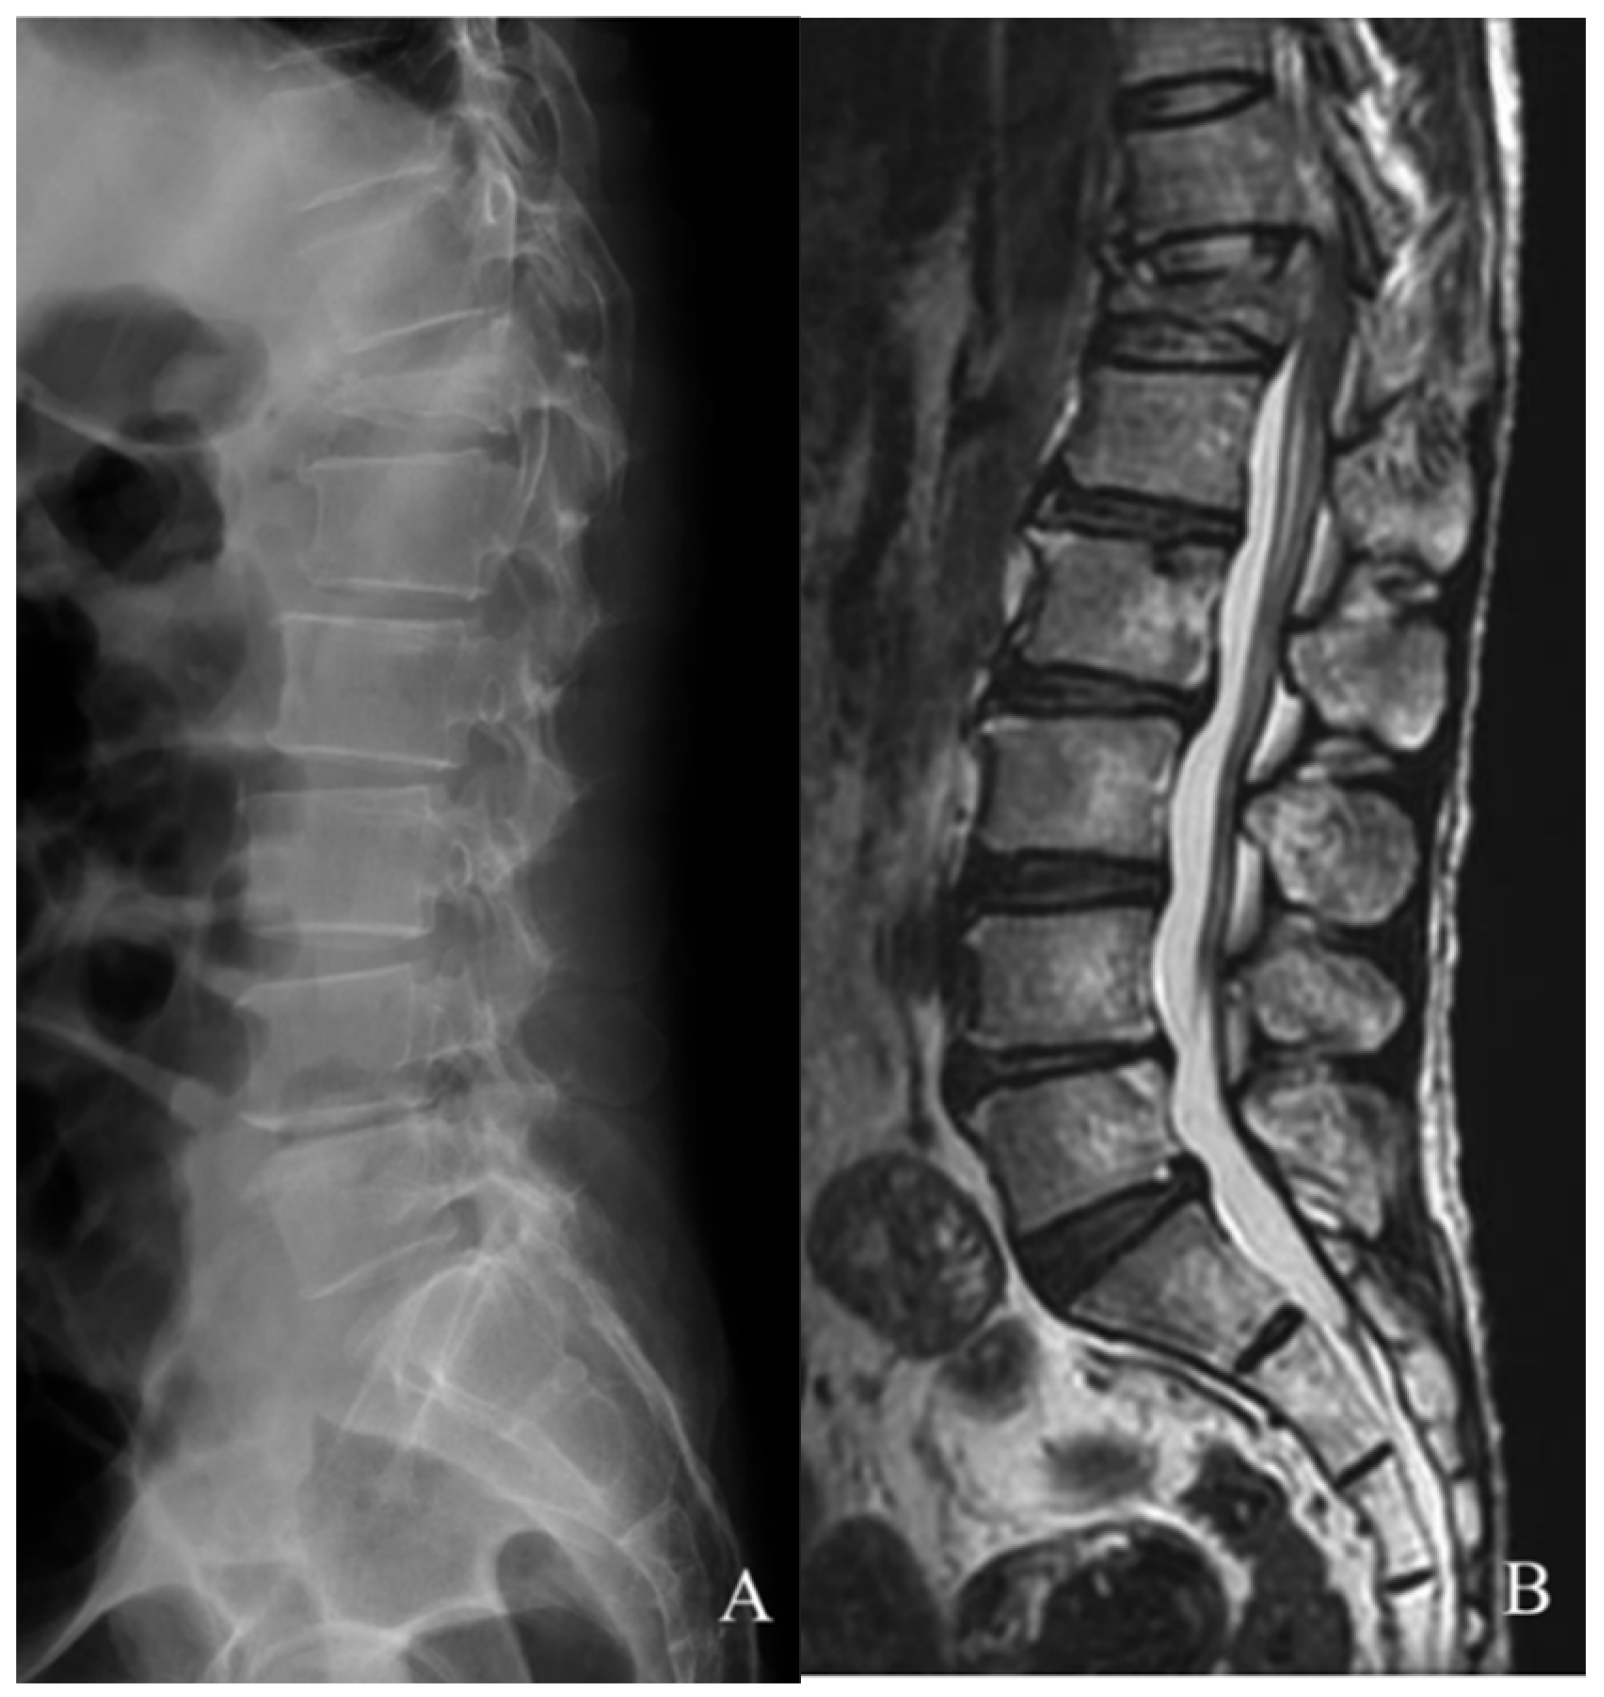

2. Case Report

2.1. History

2.2. Examination